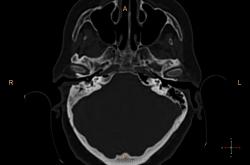

Справа в полости среднего уха небольшое количество жидкости? Пирамида и сосцевидный отросток склерозированы. У нас направляют на КТ только при подозрении на деструкцию или опухоль. Исследование выполняются на специальной программе для височных костей , срезы по 0.1 или 0.05 см, костная структура видна изумительно. А чаще изменения височных костей обнаруживаются как случайная находка при КТ черепа (хорошо видно на "сердечном" режиме).

У нас минимальный срез идет по 0,75мм, мне кажется если есть возможность провести КТ-исследование, следует это делать, что косается данной пациентки, все не так просто, у неё имеется клинически свищ с отделяемым, позади ушной раковины, где имеено и откуда идет свищ четко видно, а так все верно имеется эпитимпанит и антрит.

Согласен, ///если есть возможность провести КТ-исследование, следует это делать///, с Шуллерами-Майерами не сравнить. Кстати, состояние аттико-антральной области обычно более демонстративно на аксиальных срезах уровня латерального полукружного канала.

Касаюсь Андрей Юрьевич, лобарант меня позвал в плане выбора протокола исследования, а я при наложении плоскости сканирование на топограмме, взял и не учел оптико-меатальную линию, получилось несколько неуклюже, поэтому только на станции подорвался выравнивать её при анализе сканов :-(

Свищевой ход.